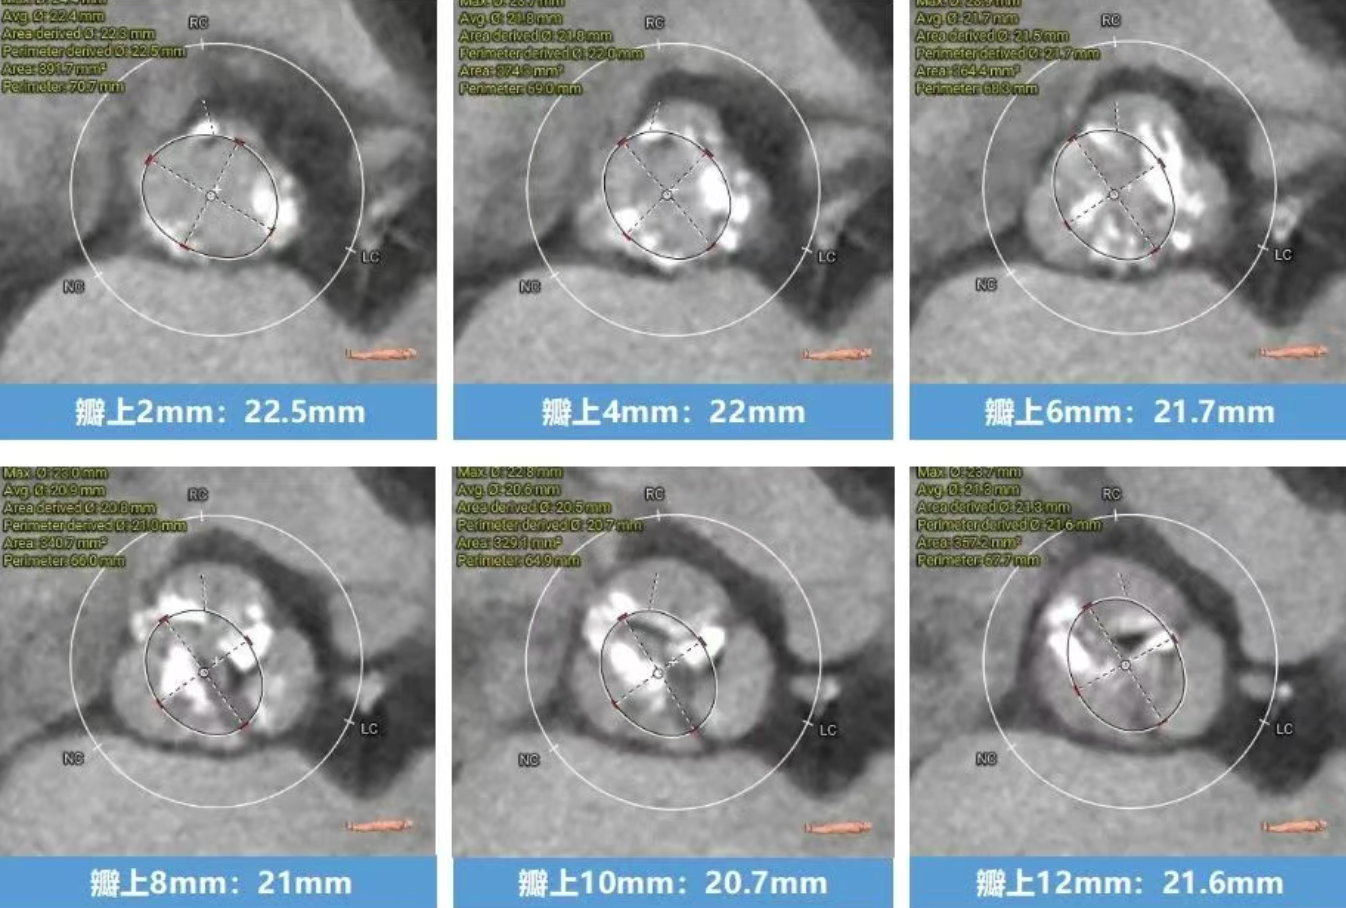

术前CT分析(76岁,女性)

▶ Type1型二叶式主动脉瓣(L-R),瓣叶增厚,重度钙化,钙化分布不均匀,无窦钙化延申至STJ以上,LVOT偏直筒型。

▶ 左右冠脉开口高度尚可,左窦瓣叶切线测量距离>冠脉开口下缘到根部距离。

▶ 心室腔内径尚可,心室壁厚度可,心尖尚可。

▶ 瓣环水平夹角72°,横位心,主动脉弓角、弓距尚可。

瓣上结构测量